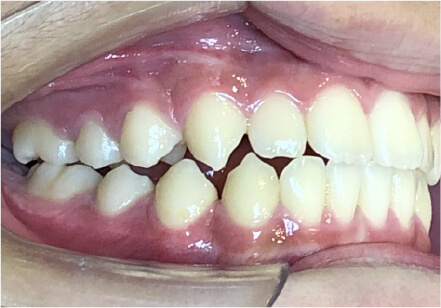

叢生の症例

13歳

男性

相談内容

マイオスマイルからの移行

カウンセリング・診断結果

治療内容・方法

全額アライナー矯正

術後の経過・現在の様子

クリアライナー使用

治療のリスク

痛み・歯根吸収・歯肉退縮・虫歯・後戻り

費用・治療期間

(インビザのみ)745,000円、1年11ヶ月